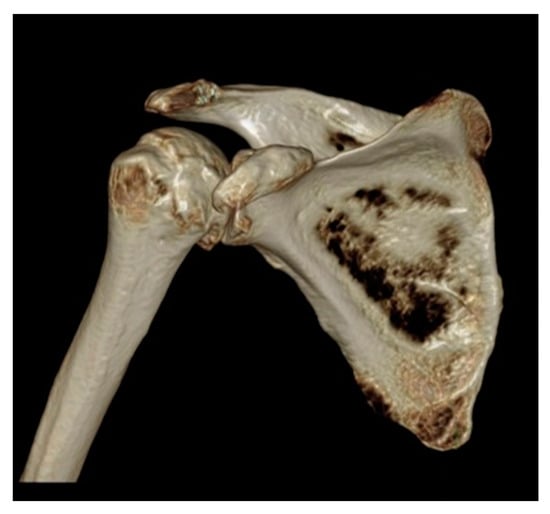

3. Preoperative Imaging

5.2. Reverse Arthroplasty

Reverse Total Shoulder Arthroplasty (RTSA)